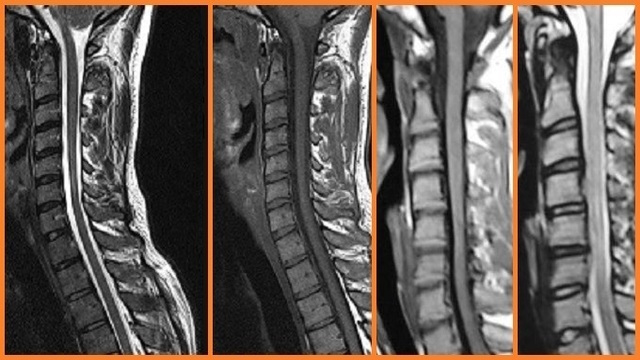

Hastalığın radyolojik tanısında MRG ( Manyetik Rezonans Görüntüleme ) tetkiki ön plandadır. Çeşitli MRG bulguları tanımlanmıştır. Bunlar başlıca; lokalize alt servikal kord atrofisi, asimetrik kord düzleşmesi, alt servikal kordda parankimal sinyal değişiklikleri, anormal servikal kurvatur, posterior dural kese ve altındaki lamina arasındaki bağlantının kaybolması, servikal dural kanalın posterior duvarının anteriora doğru şifti, posterior epidural alanda genişleme, alt servikal ve torasik bölgede kontrast tutan epidural komponent ve dilate epidural venöz pleksusu düşündüren belirgin epidural alanda akıma bağlı sinyal kayıpları olan alanlardır. Yine sıklıkla asimetrik/simetrik alt servikal kord atrofisi, fleksiyon çalışmalarında posterior epidural venöz pleksusta belirginleşme ve kontrast tutulumu, posterior duranın anteriora doğru şifti görülebilir. Özellikle nötral pozisyonda posterior dural kese ve altındaki lamina arasındaki bağlantının kaybı, fleksiyon çalışmalarında servikal dural kanalın posterior duvarının anteriora doğru şifti ve kontrast tutan epidural komponent ile dilate epidural venöz pleksusu düşündüren alanlar yüksek oranda hirayama hastalığını düşündürmelidir.

Değişiklikler sıklıkla C6 vertebral düzeyde en belirgindir. Literatürde Hirayamalı hastalarda rutin MRG çalışmalarında özellikle alt servikal bölgede asimetrik kord atrofisi tanımlanmıştır. Elleri ve/veya ön kolunda kas atrofisi olan genç bir hastada bu bulgular izlendiğinde Hirayama hastalığı kuşkusu oluşmalı ve fleksiyon MRG çalışması tanıyı konfirme etmek için yapılmalıdır.

MRG Hirayama hastalığının tanısında son derece yardımcıdır. Fleksiyon çalışmaları bu hastalarda MRG protokolunun temel parçası olmalıdır.